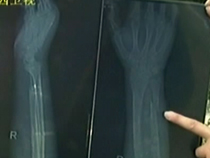

小腿骨折去醫(yī)院 醫(yī)腿未成險(xiǎn)廢手